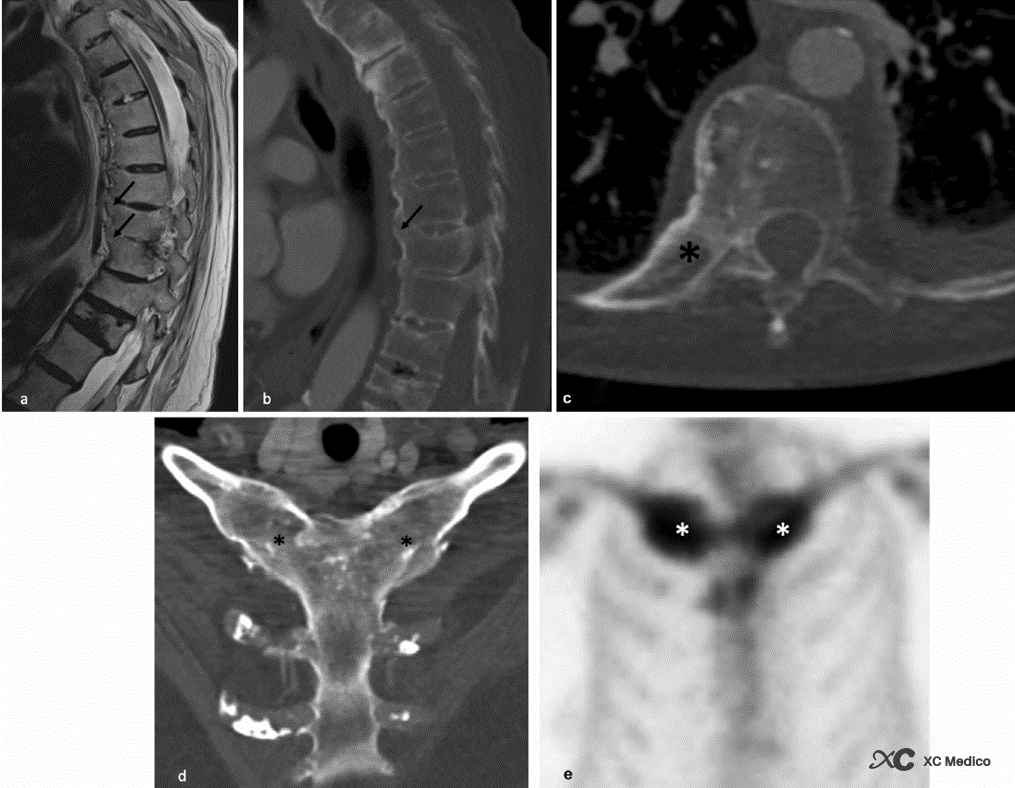

Poznámka: 62letý muž se syndromem SAPHO. (a) Sagitální t2-vážené snímky a (b) snímky z počítačové tomografie (CT) ukazují osifikaci předního podélného vazu (černé šipky) Žádné významné abnormality ploténky nebo paravertebrální tekutiny. L1 je vysoce přemístěna po staré kompresní zlomenině. (c) Axiální CT ukazuje ankylózu pravého kostovertebrálního kloubu (hvězdička). (d) Šikmá koronální CT rekonstrukce ukazuje bilaterální ankylózu klíční kosti hrudního žebra (černé hvězdičky). (e) Kostní sken ukazující vychytávání radioindikátoru v obou postižených kloubech (bílé hvězdičky).

Poznámka: 58letý muž s neuropatickou páteří. (a) Sagitální a (b) koronální počítačové tomografické rekonstrukce ukazují mnohočetné bederní vertebrální koncové ploténky a kloubní synoviální kloubní eroze (šipky) s kostními fragmenty. Destrukce jednotky meziobratlové ploténky L2-L3 s rozšířením meziobratlového prostoru (hvězdička). (c) Sagitální a (d) axiální t2-vážené sekvence magnetické rezonance potvrzující rozšíření intervertebrálního prostoru L2-L3. významné změny postižené míchy za L2-L3-L4. Existuje také výpotek v měkkých tkáních za a před trnovými výběžky (hvězdičky).